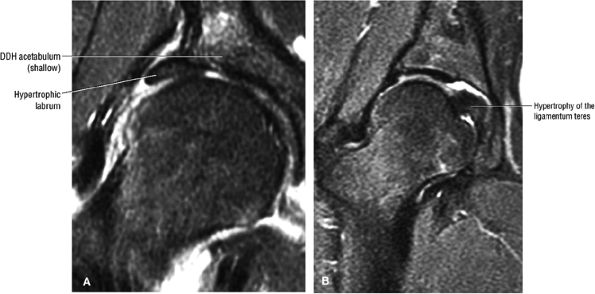

In DDH the labrum may be hypertrophic and associated with a femoral head chondral crease.

An anterosuperior cleft (Fig. 3.61) may be seen as a normal variant in the presence of a normal lateral acetabular labrum. On anterior coronal or sagittal images, this cleft is seen as a partial undercutting of the labrum on a single image. The extension of fluid into this cleft occurs from the femoral side. It may be more commonly seen in labral hypertrophy associated with mild developmental dysplasia of the hip (DDH).

An enlarged or hypertrophied labrum may occur in patients with mild DDH.17 We have observed a femoral head chondral crease (Fig. 3.66) in these patients, creating a demarcation trough medial to a femoral head bump immediately proximal to the physeal scar. Patients who demonstrate femoroacetabular impingement (or lateral acetabular rim syndrome in DDH) also have direct impingement between the lateral acetabular labrum and the femoral head.

FIGURE 3.101 ● (A) DDH associated with longitudinal tearing of a hypertrophied labrum. The shallow slope of the acetabulum is demonstrated. The transverse angle of the osseous acetabular rim affects the degree of lateral coverage and is increased in adult DDH. (B) The normal angle of 40° is shown in contrast to (A).

FIGURE 3.102 ● (A) Labral hypertrophy in DDH. (B) Mild labral hypertrophy and marked hypertrophy of the ligamentum teres in DDH. Coronal FS PD FSE images.

patient. Unfortunately, the hypertrophic labrum is exposed to greater joint reaction forces and is at an increased risk for symptomatic tearing. The acetabular labrum may also become inverted, entrapped, and subsequently torn. Direct contact between the hypertrophied labrum and the femoral head chondral surface may produce a chondral crease demarcating a femoral head bump formed proximal to the physeal scar. This finding is associated with a lateral acetabular rim or the DDH equivalent of FAI. Anterior coronal MR images evaluated at the level of the anteriormost portion of the femoral head are sensitive to asymmetry in the slope of the acetabulum. The anterior acetabular roof should maintain a relatively horizontal slope and not open up or deviate from the horizontal plane.